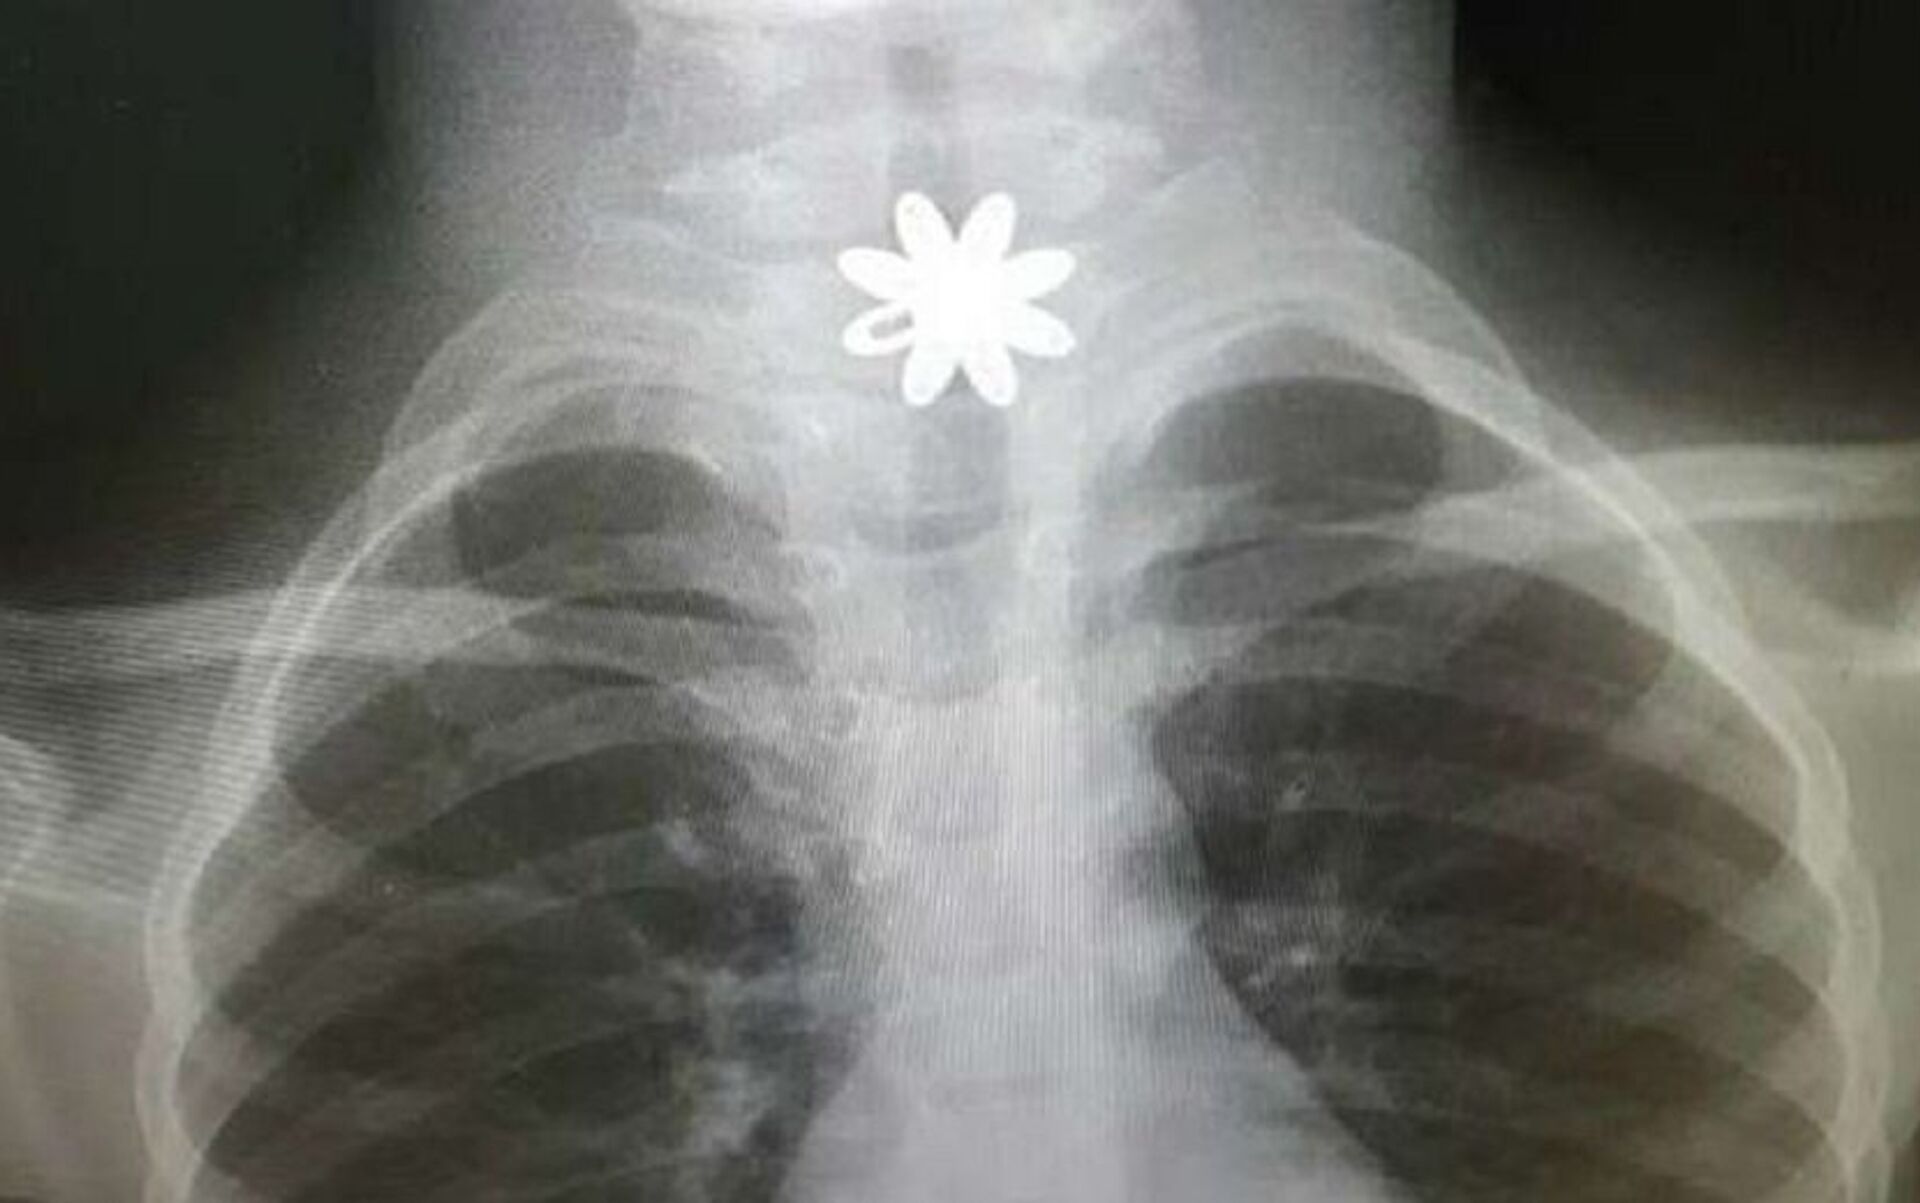

وفي التفاصيل، تم إدخال الطفلة إلى المستشفى وهي تعاني انسدادا في المريء، وبعد تشخيص الحالة، اتضح وجود قطعة معدنية حادة تشكل خطورة على حياة الطفلة، ممّا أدى إلى جروحٍ قطعية داخل المريء، بحسب "المواطن".

وخضعت الطفلة لعملية باستخدام منظار المريء الصلب، لاستخراج القطعة المعدنية، في وقت قياسي وبشكل دقيق وسريع، وتمّت معالجة الحالة، حيث غادرت المستشفى بصحةٍ جيدة.